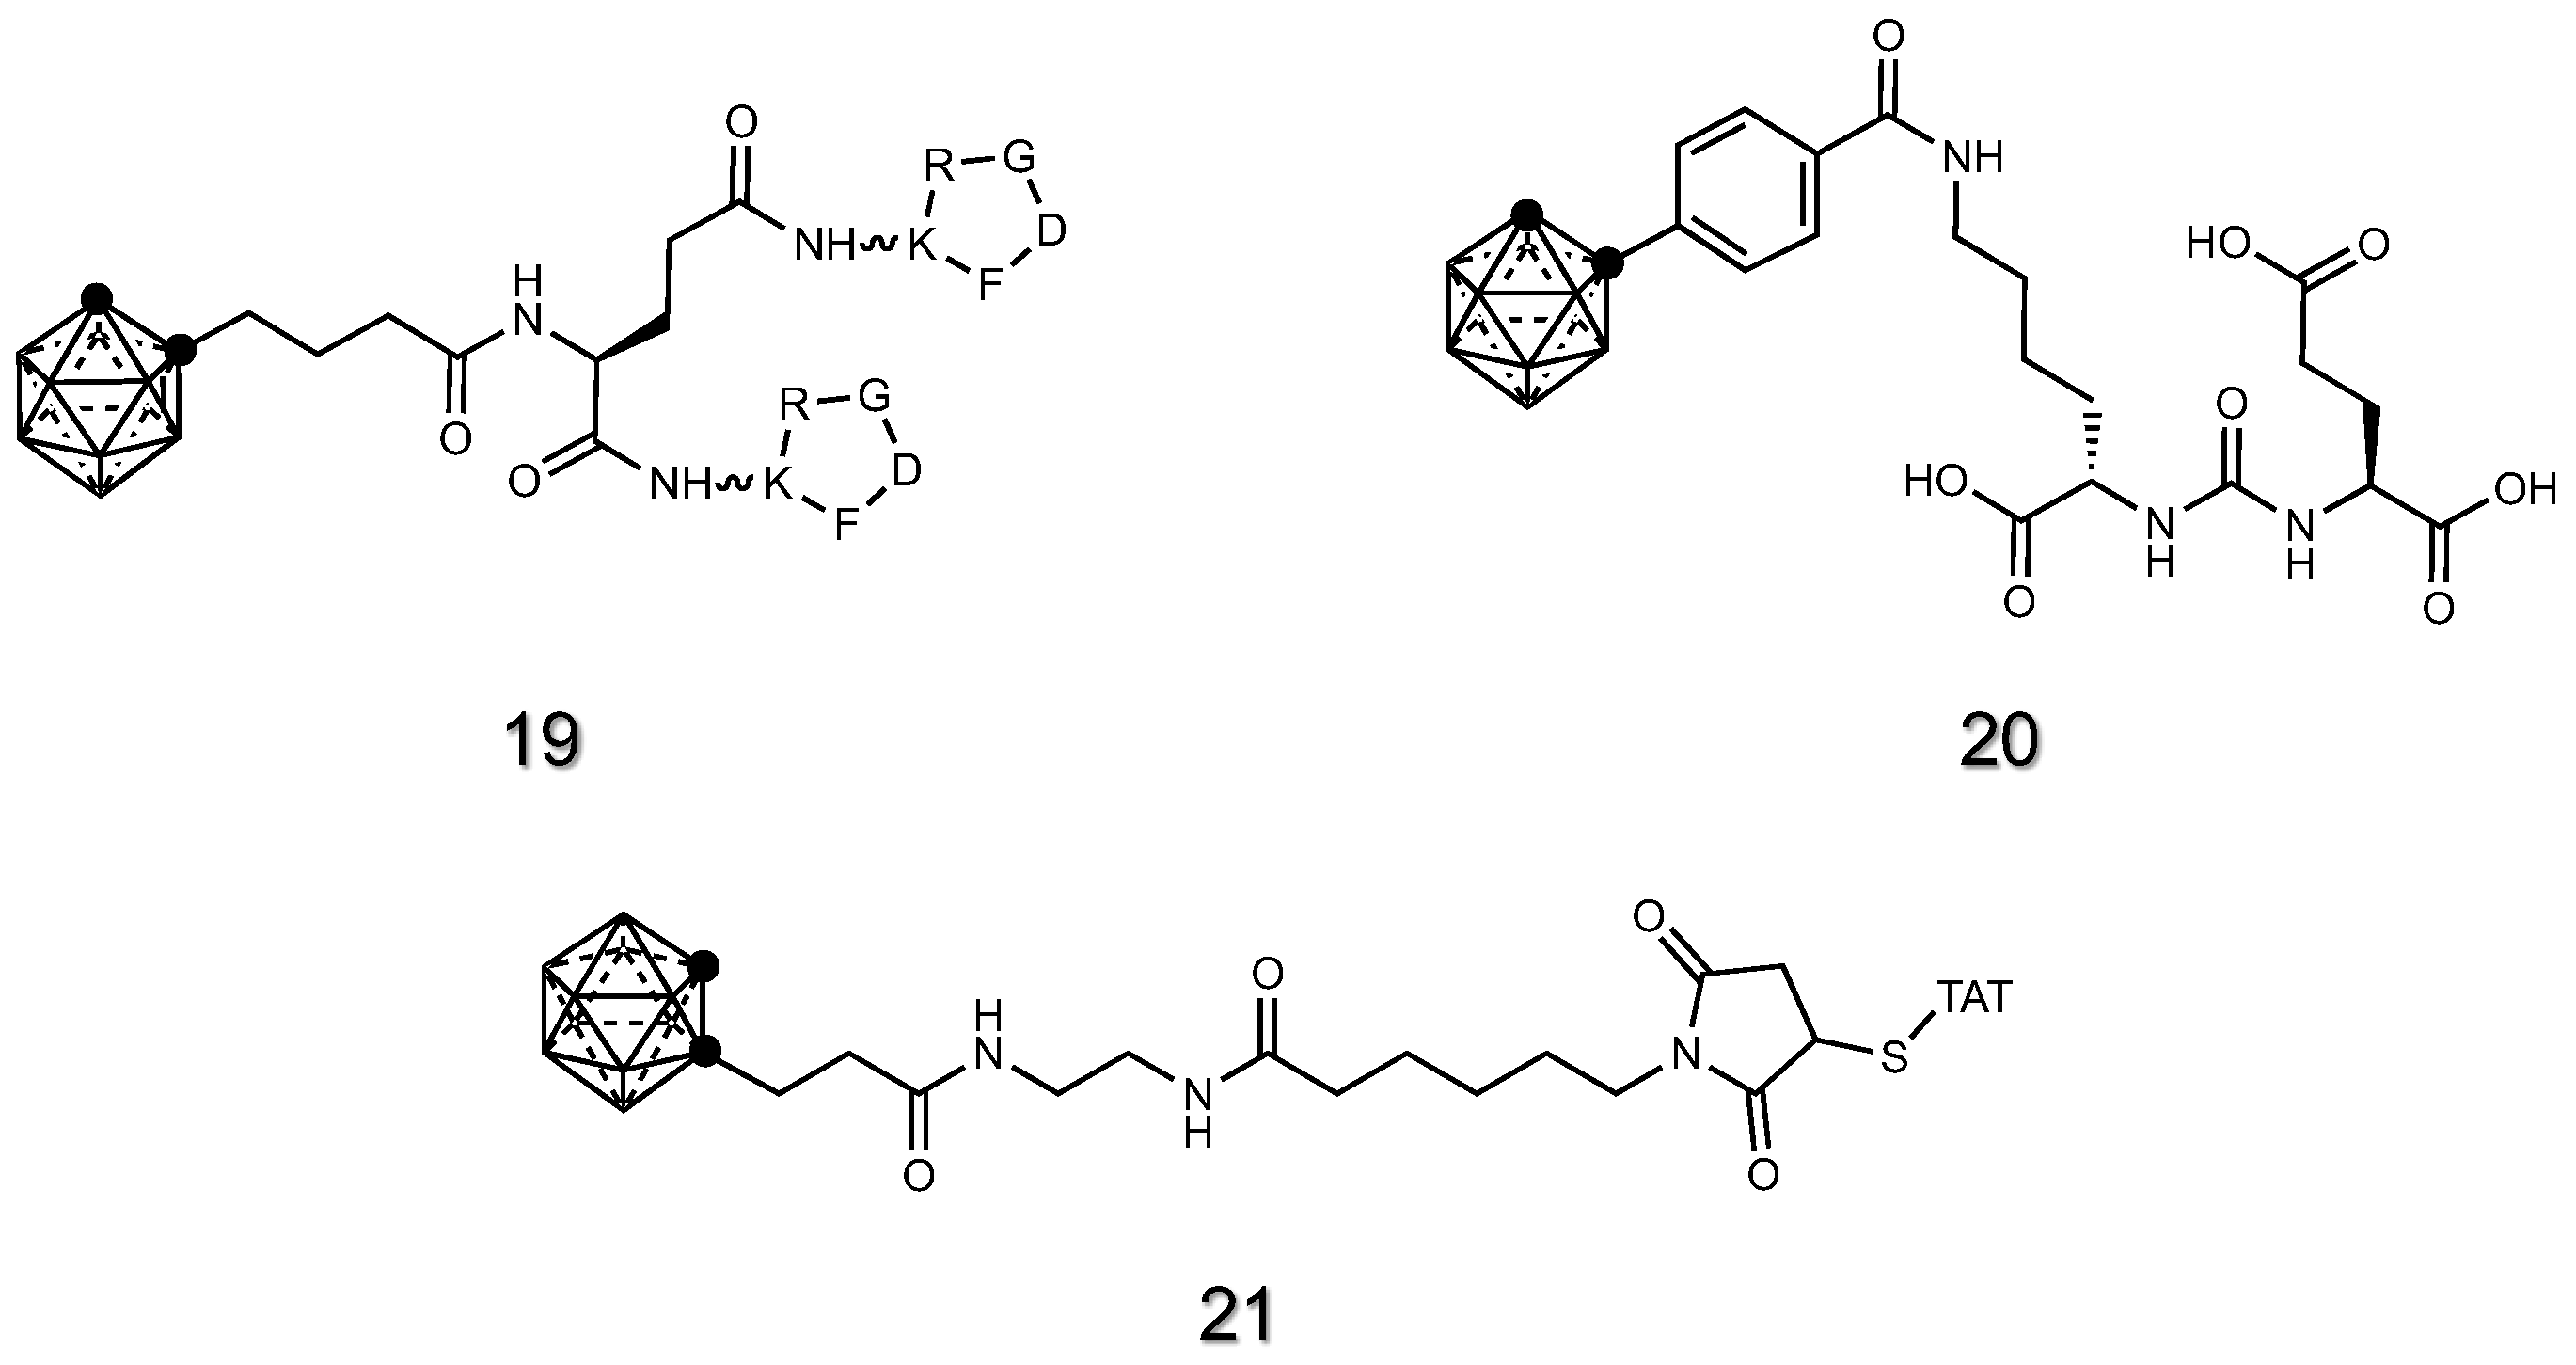

2.1.7. Peptide Derivatives of Carboranes

2.1.8. Antibody Derivatives of Carboranes